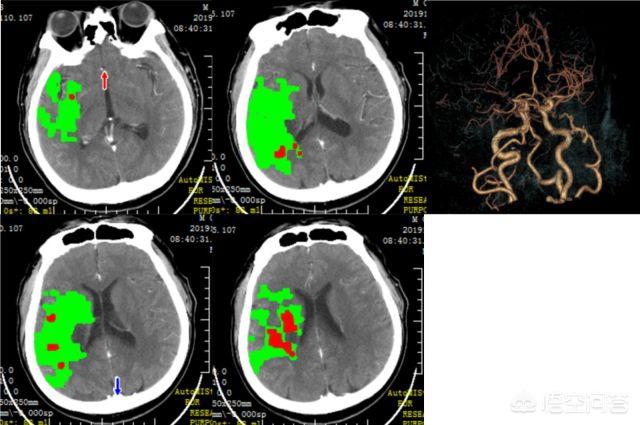

脳梗塞の治療は急性期と慢性期に分けられる。脳梗塞の超急性期、すなわち虚血性脳卒中では、通常、静脈内血栓溶解療法か動脈カテーテル血栓溶解療法を行います。静脈内血栓溶解療法や動脈カテーテルによる血栓溶解療法が可能な期間を超えた場合は、一般的な薬物療法、いわゆる血管拡張療法、うっ血の活性化療法、抗血小板療法などを行う。脳梗塞の1ヵ月後には脳血管造影を行い、脳梗塞の原因が脳狭窄であることがわかれば、ステント治療を行うこともあります。

脳梗塞の一般的な黄金治療は発症から6時間以内であり、適切かつタイムリーな治療により、虚血した横隔膜を可能な限り保護することができる。脳梗塞の治療は一般にこの3つから始まる:

脳血液循環の改善:血栓溶解療法、抗血小板凝集療法、抗凝固療法、線維減少療法、容積拡大療法など。

神経保護:神経保護剤は脳細胞を保護し、虚血や低酸素に対する耐性を高めると理論づけられている。

その他の治療法。神経損傷を軽減し、神経機能の回復を促進するブチルフタリドなど。